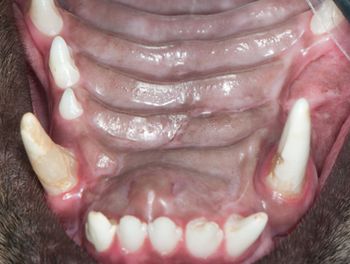

DEK Bulldogs, Labrador retrievers and beagles are prone to it. Why, what is it, and what can be done?